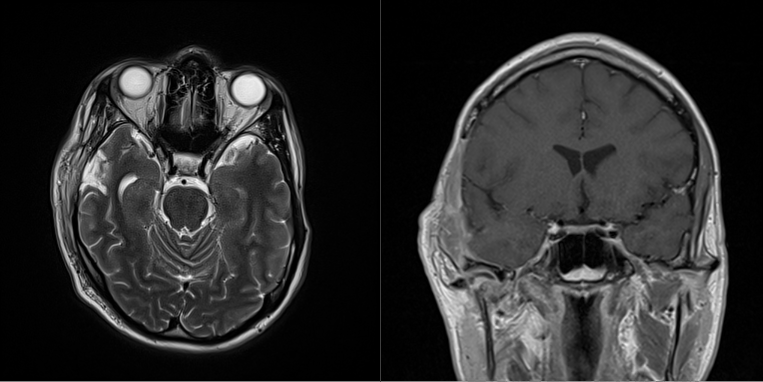

Two months after his injury, the patient developed purulent drainage from the scalp surgical wound (Figure 15). He was started with vancomycin and cefepime empirically. Magnetic resonance imaging showed a fluid collection concerning for abscess; therefore, he was taken to the OR for irrigation and debridement (Figure 16). Intraoperative cultures grew Staphylococcus epidermidis, and the patient was placed on 6 weeks of IV vancomycin for cerebritis. Four months following his initial injuries, he underwent a cranioplasty with a PolyEtherEtherKetone (PEEK) implant fully covered by a temporalis muscle flap. There were no postoperative complications, and the patient was healing well at his 6-month follow-up without any malocclusion or wounds (Figure 17).

Figure 16. Case 3: (left) axial and (right) coronal magnetic resonance imaging of the presentation with purulent discharge.